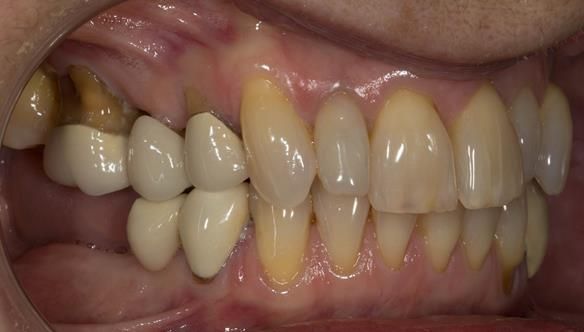

This newsletter describes in step by step detail Angela's transition through immediate partial dentures to crown supported definitive metal based dentures.

This 58 year old woman was referred to me by her general dental practitoner for treatment.

- Generalised Periodontitis; Stage 4, Grade C, Currently Unstable. Risk Factors: Type 1 diabetes. 16, 17 - hopeless prognosis. 14, 24, 26, 27, 34, 37, 44 - guarded prognosis

- Poor marginal fit and poor appearance of crowns and bridgework

- Yellowing teeth

The clinical situation and treatment process is shown in detail below with photographs. I (Finlay Sutton) provided the clinical work and Rowan Garstang provided the technical work.